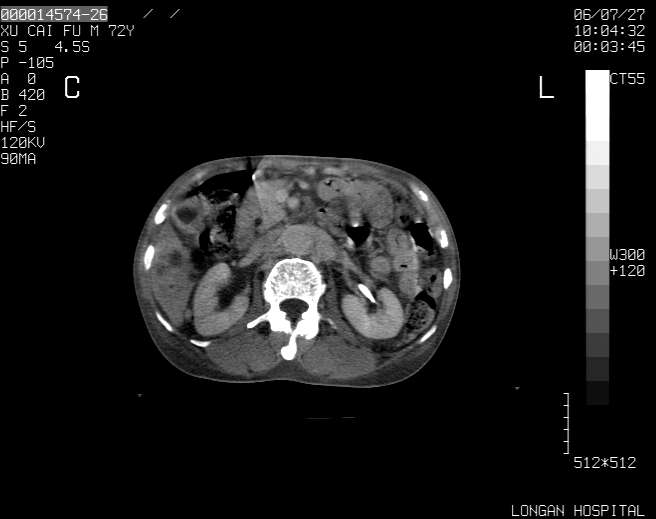

以下是引用winter在2006-7-30 20:14:00的发言:[br]1、考虑胆囊癌伴胆道侵犯并高位胆道梗阻、肝内多发转移、腹膜后淋巴结转移。[br]2、右肾轻度积水。[br]3、老人家72岁了胰腺头体尾部均较饱满,不过未见密度异常及其他异常征象。[br]4、腹水。

以下是引用jiajie在2006-7-31 7:10:00的发言:[br]考虑肝转移瘤,腹膜后淋巴结增大。[br]胃癌不能除外,建议胃镜检查。